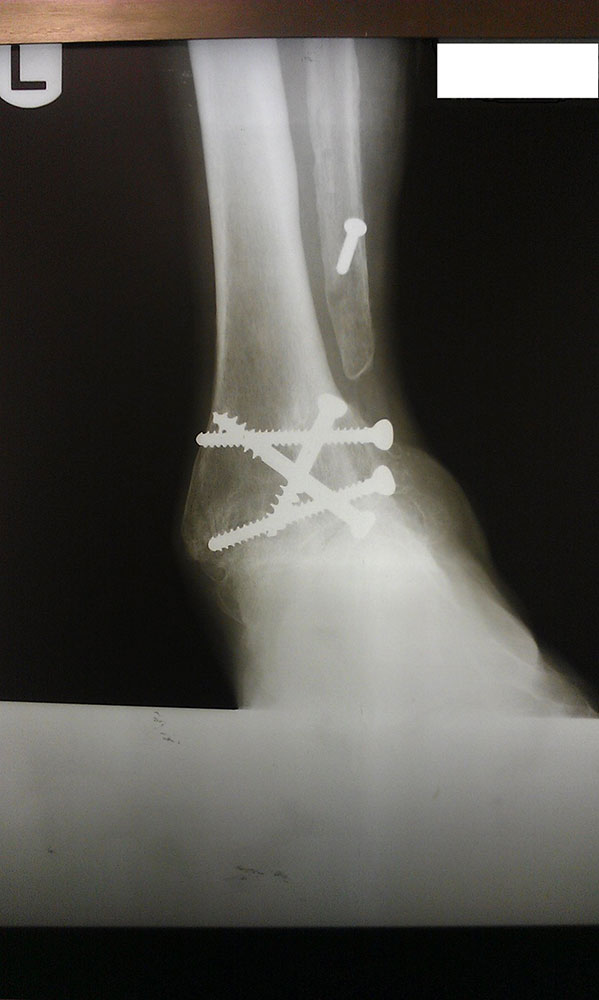

"Surgical misadventure" by another surgeon about 8 years ago. The wrong fixation was used for a flatfoot repair, & the deformity was not corrected. Patient came in with severe foot & ankle pain, with no arch at all. She was unable to play with her grandchild because the pain was so bad, & because she felt unsteady. The old hardware was removed, a lateral calcaneal lengthening osteotomy was performed along with a medial column/1st ray realignment. The ankle was painfully arthritic, & patient elected a total ankle replacement vs. an ankle fusion. She is now able to walk pain free & play with her grandchildren!